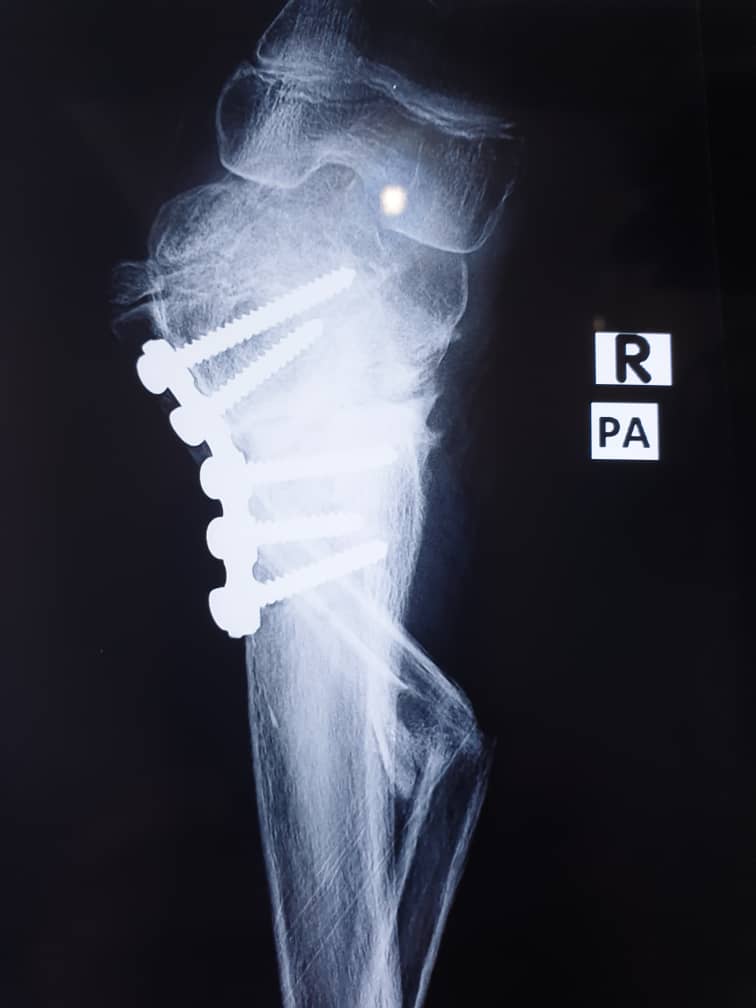

2023 Surgical Support for

a Young Girl in Need

In 2023, the Sons of Nigeria undertook a remarkable project to support a young girl, who required surgical correction for a severe leg condition. With compassion and collective effort, SON members made it possible for her to undergo corrective surgery—restoring hope, mobility, and a brighter future.